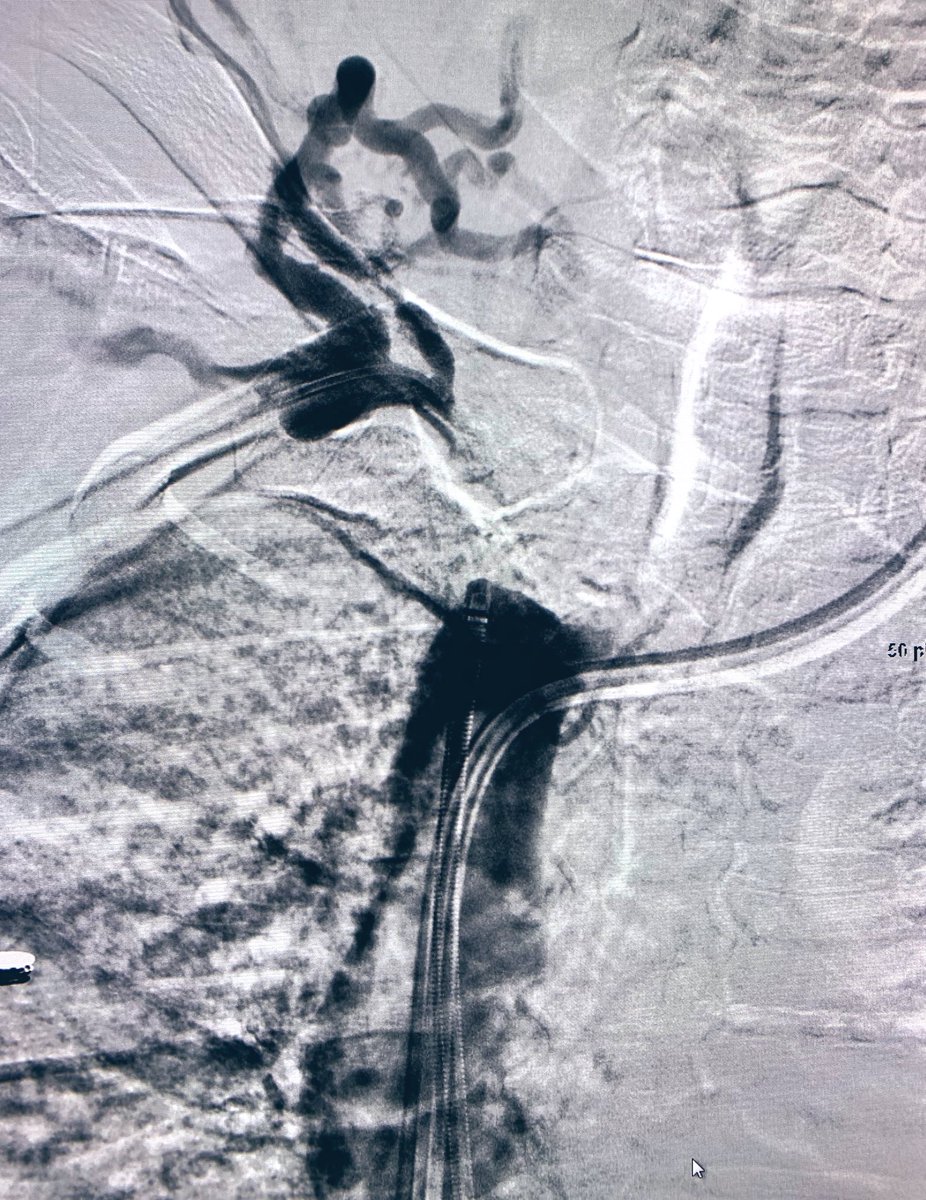

#venousreconstruction for b/l#legswelling.#IVC#occlusion from#filter placed 6 months ago for DVT and brain bleed. 2 IR effort ( Dr. Gordon).#filterretrieval followed by#iliocaval#stenting with#venovo.#irad#twittIR@SIRspecialists@SIR_ECS@SIRRFS@JVIRmedia@PairsWebpic.twitter.com/PqlCM1BJxL